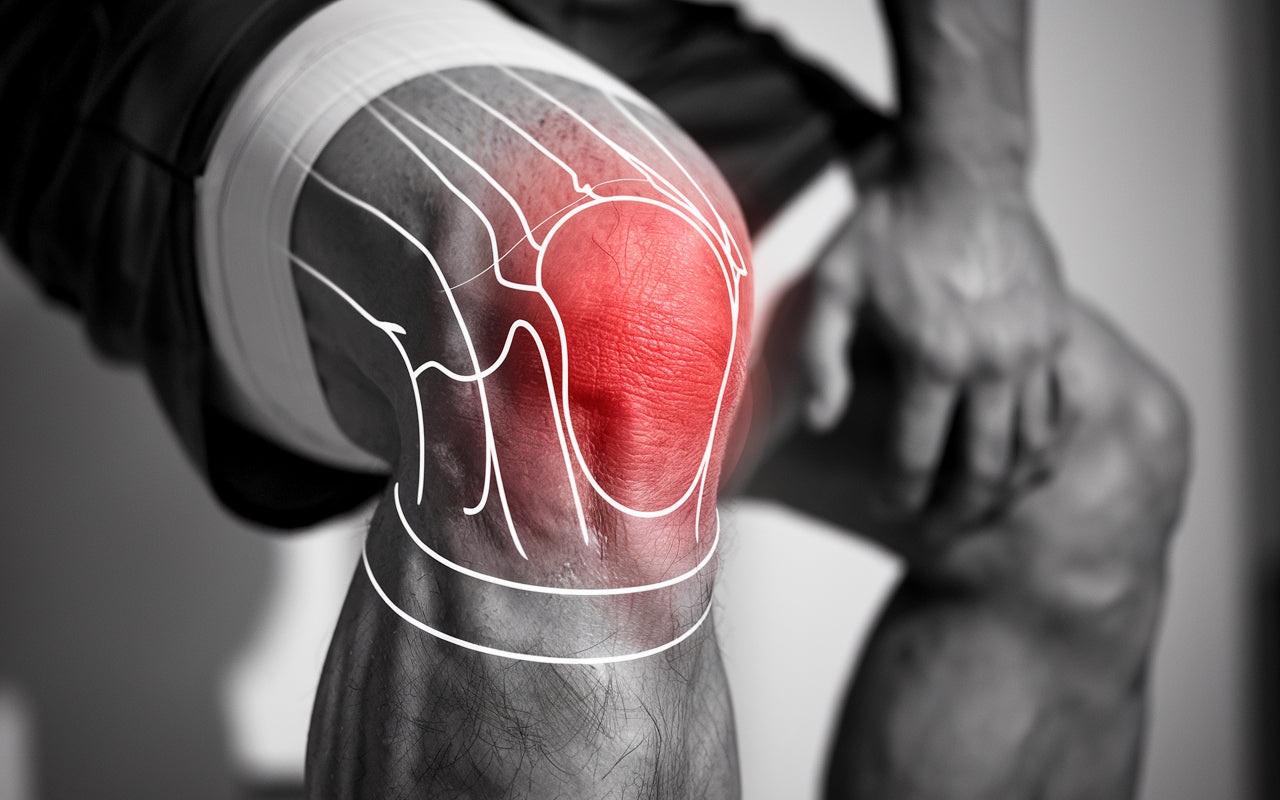

Knäleden är en av kroppens mest komplexa leder och utsätts dagligen för stor belastning. Knäproblem kan drabba personer i alla åldrar och uppstår av många olika orsaker.